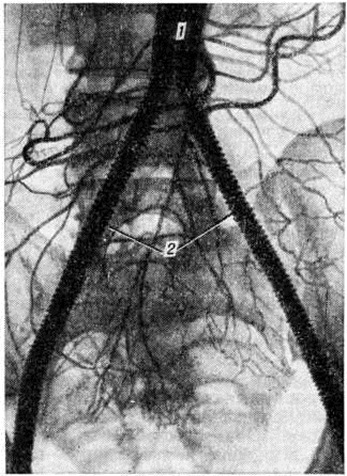

Топическую картину поражения можно установить пробой изотопной и рентгеноконтрастной ангиографии. Изотопная ангиография (смотри полный свод знаний) осуществляется пробой внутривенного введения технеция 99-м. Из методов рентгеноконтрастного исследования предпочтение следует отдать транслюмбальной пункционной аортографии (смотри полный свод знаний), при которой возможно получить изображение не только аорты, но и дистального сосудистого русла конечностей. Именно аортография выявляет локализацию и протяжённость поражения (рисунок 4—6), однако её следует проводить только при решении вопроса об оперативном лечении больного.